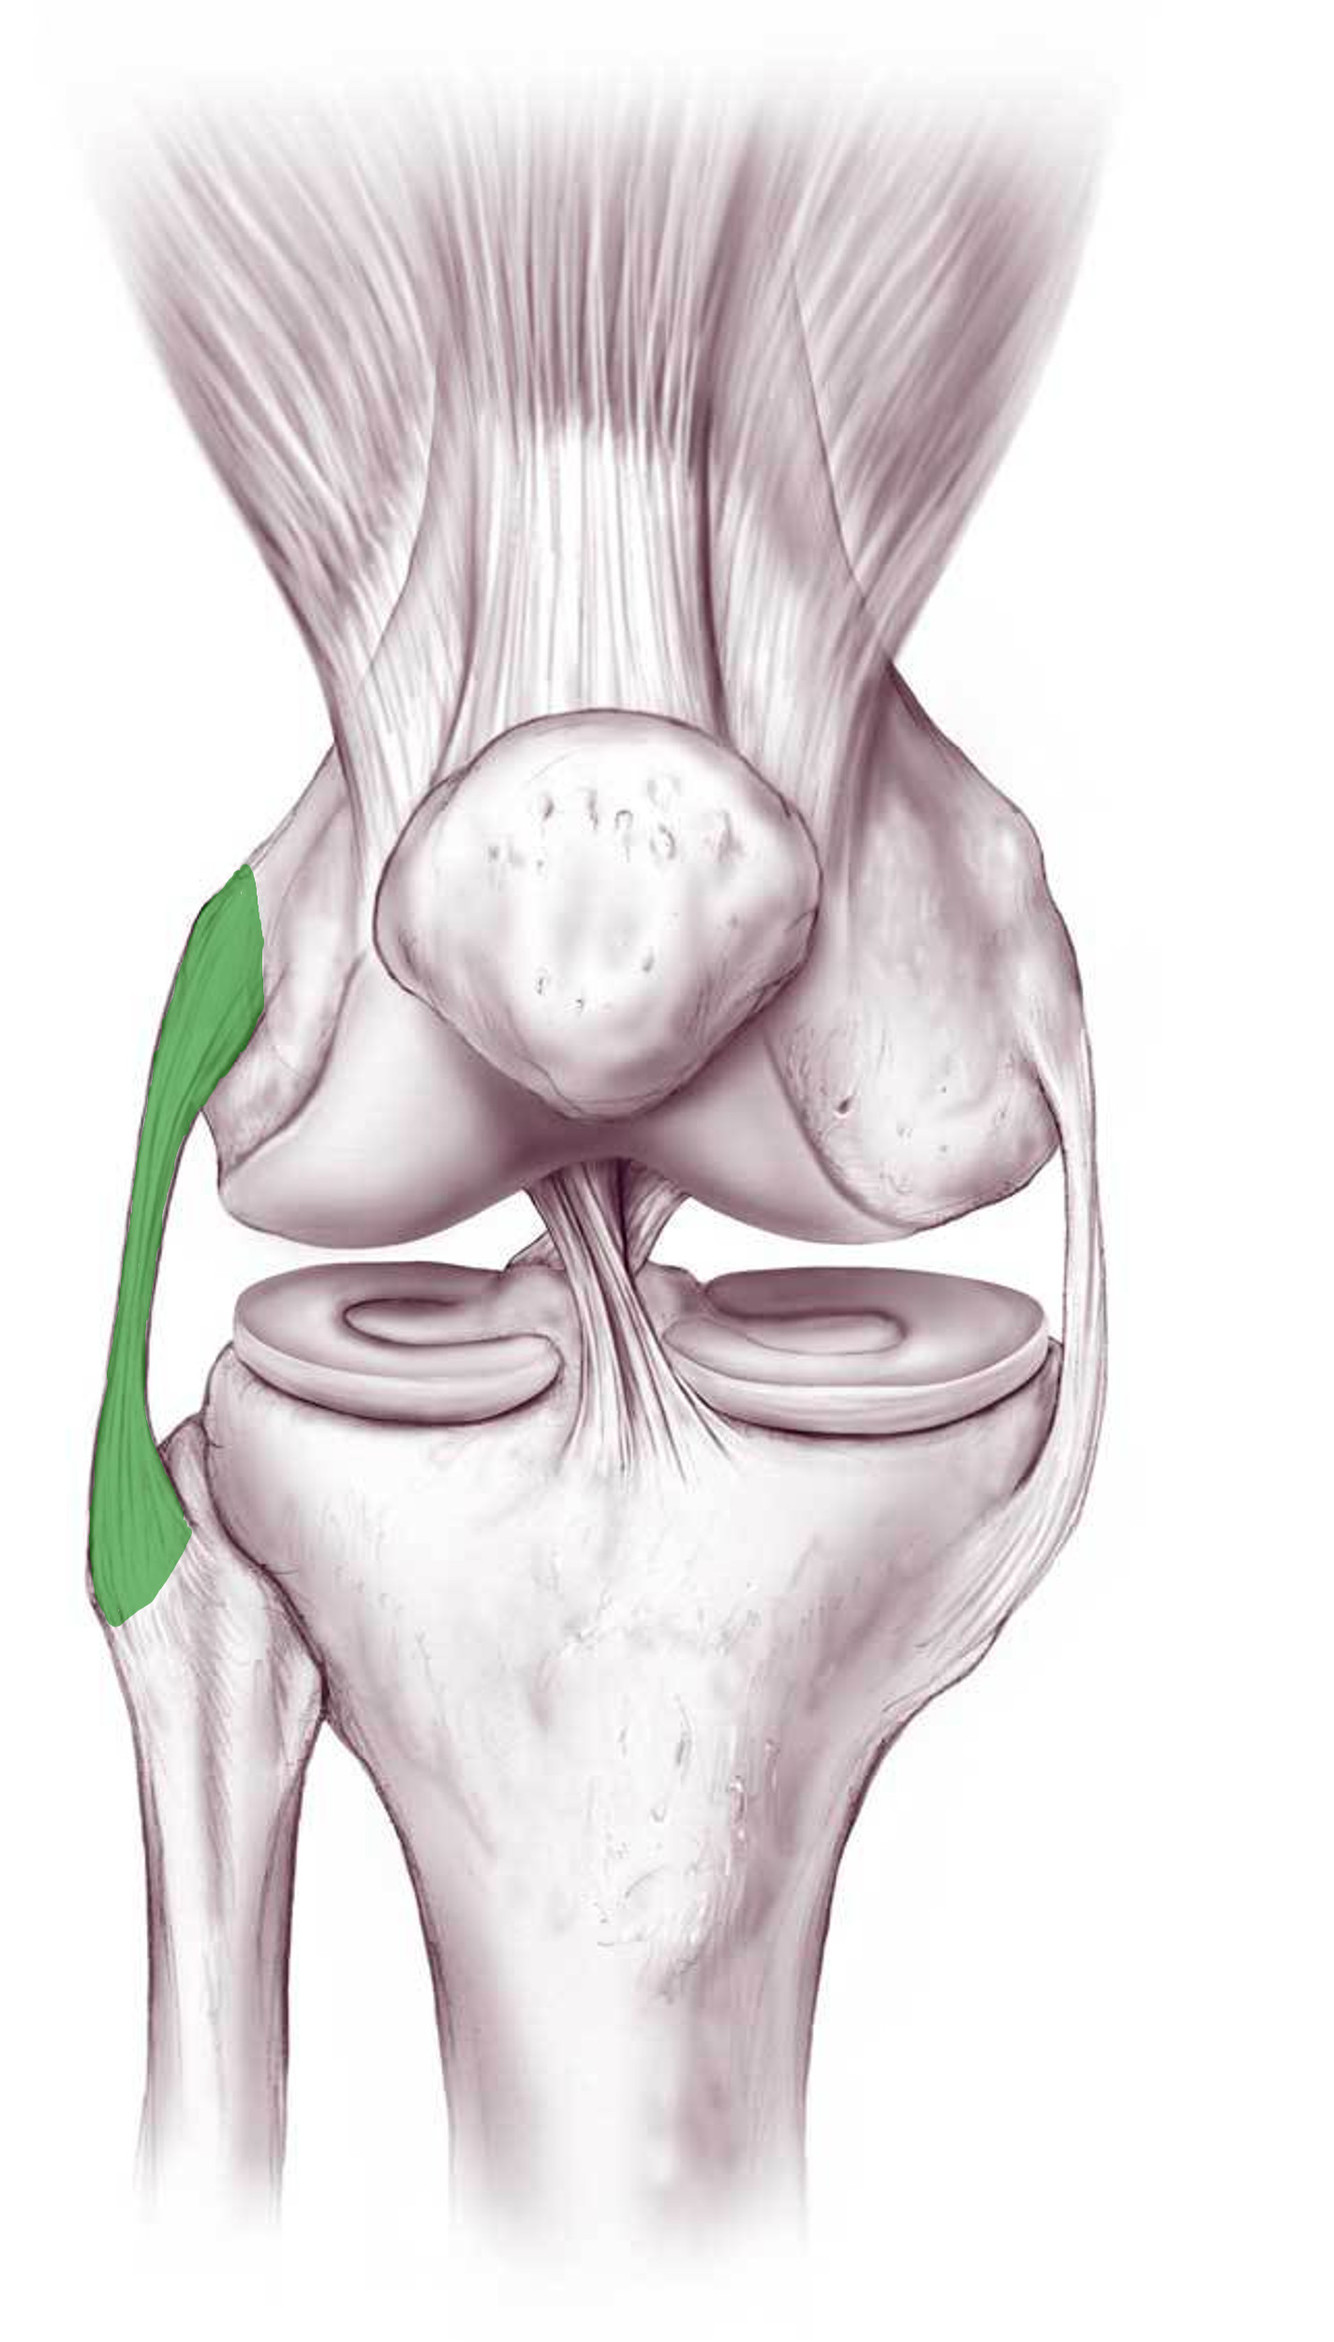

What is this structure?

Lateral collateral ligament of the knee

Where does the lateral collateral ligament extend to and from?

Lateral epicondyle of femur

to lateral surface of head of fibula